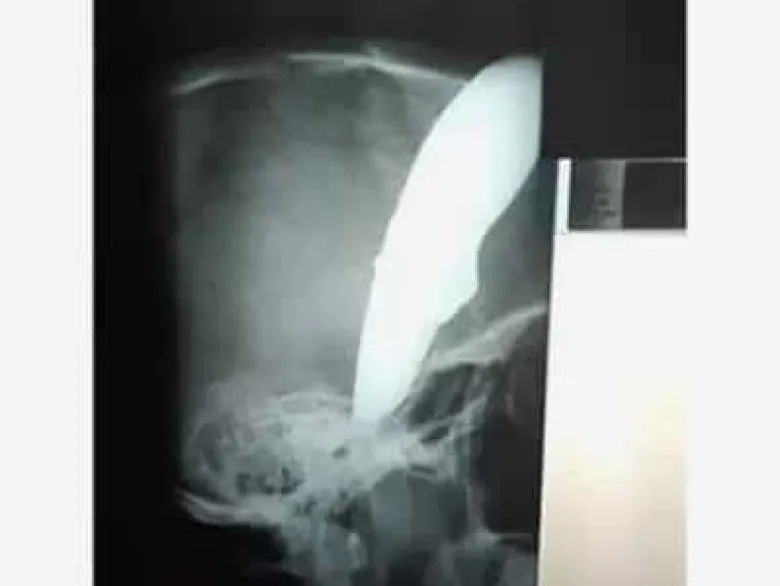

Քեյփթաունի բնակիչ Շոն Ուեյնը հարձակման է ենթարկվել եւ եկել է հիվանդանոց դանակը գլխին, հայտնում է Daily Mail պարբերականը։

Միջադեպը տեղի է ունեցել երկուշաբթի՝ նոյեմբերի 19-ին։ Տղամարդը հեծանիվով գնալիս է եղել սուշի ռեստորան աշխատանքի, երբ նրա վրա են հարձակվել երկու չարագործներ։ Նրանցից մեկը 34-ամյա Ուեյնի գլխին է հարվածել դանակով, իսկ 15 սանտիմետր սայրը մնացել է գանգի ներսում։ Հանցագործները փորձել են նրանից խլել հեծանիվը, բայց նրան հաջողվել է իրեն պաշտպանել, նրան ծեծել է եւ հեռացել։

Բժիշկների խոսքով՝ պացիենտի բախտը բերել է, որ սայրը չի մտել գանգը։ Ուեյնին անհապաղ վիրահատություն են արել, նրա վիճակը կայուն է։